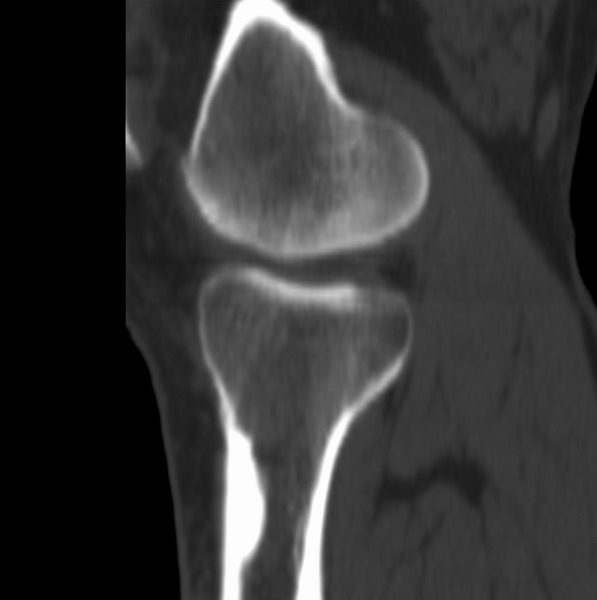

右侧膝关节疼痛一月

男、48

股骨下段、胫骨上段。

股骨干骺端病变考虑非骨化性纤维瘤。

1、股骨干骺端病变考虑干骺端纤维性皮质缺损愈后(非骨化性纤维瘤)改变,胫骨近端内生骨瘤;

2、骨关节炎,骨质增生,股骨外侧髁退变性囊肿(关节面软骨下囊肿);